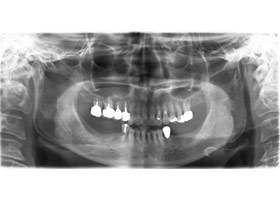

治療前全口x光片、口內照片

術前缺牙無法咀嚼